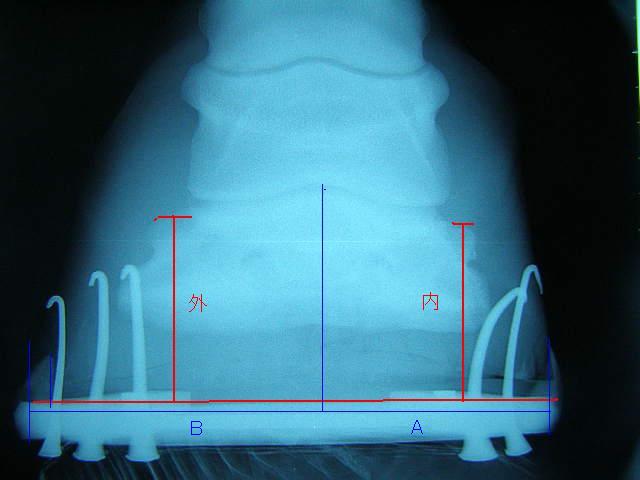

装蹄に先立ち、治療開始3ヶ月後のレントゲンを撮りました。

昨年9月のものと比較してみます。

今回の左前肢

ラメラーウェッジがだいぶ取り除かれ、蹄が蹄壁にきちんとくっついて生えてきているのが確認できてホッとしました。

この写真を参考に、装蹄を行ないました。